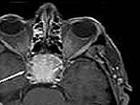

确诊需依据病理诊断。颅底X、颅正侧位、CT、MRI可显示斜坡、蝶鞍、尖等处有质破坏及肿块阴影有助于诊断,须与部其他肿鼻咽纤维鼻咽癌、等相鉴

多位于鼻咽,随着肿增大,常有头痛、进鼻塞、脓性涕、鼾声、嗅觉减退、耳鸣耳聋等。发生于口咽、下者较少,可有吞下不适及出现呼吸困难。肿向颅发展,可出现颅神经受累的症状。查体可见鼻咽壁、后壁、侧壁上有肿块隆起,基底广,触之稍硬,表面有正常粘膜。